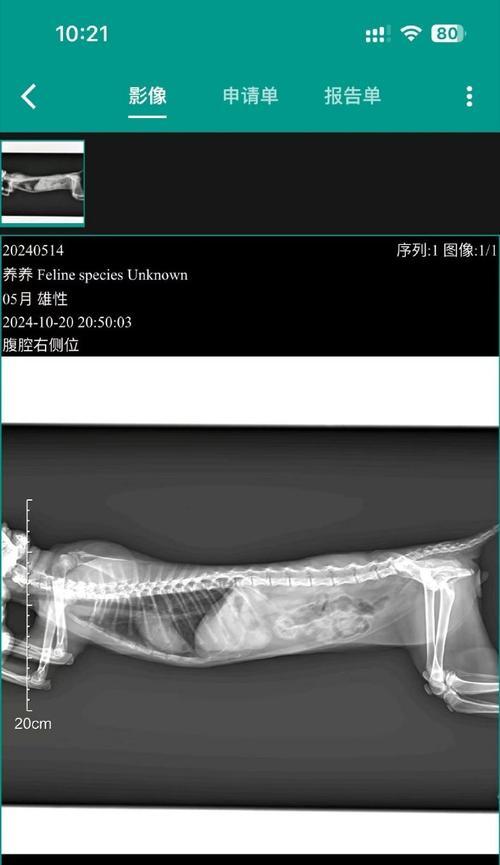

在这个阶段,胎儿的骨骼开始形成,进行X光检查可以更清楚地观察胎儿的发育情况。但仍需注意控制辐射剂量,以减少对母犬和胎儿的伤害。

怀孕后期:第12-14周

在怀孕后期,胎儿已经基本发育完全。进行X光检查可以清楚地观察胎儿的位置和数量,并排除任何异常情况。